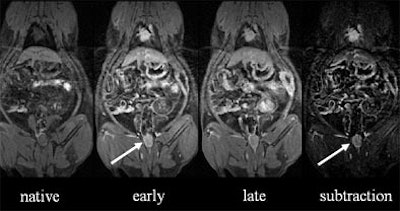

| (Left to right) The animal's chest and abdomen can be seen in the native unenhanced dataset, along with some motion artifact. Image quality improves slightly in early phase contrast, and significantly in late-phase contrast, four to five minutes after intravenous administration. Subtracting the native dataset from the early or arterial-phase dataset increases conspicuity of the colorectal lesion (arrow). All images courtesy of Dr. Christoph Herborn. |